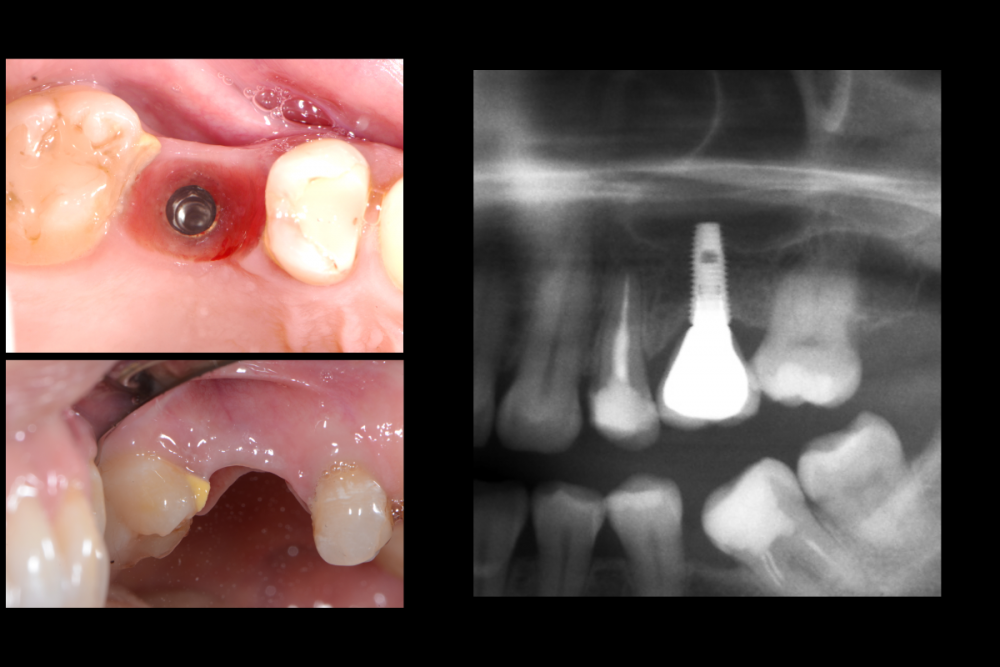

Карен Аванесов Опубликовано 10 июля, 2021 Поделиться Опубликовано 10 июля, 2021 В одноимённой теме топикстартера Женьки (Евгений неплохой человек, культурный, не хамит, а профессиональная уверенность придет с опытом, выше нос!), так вот, я высказал свое решение для реализации клинической ситуации. Это не уникальная ситуация и на мой взгляд не требует усложнений, усложнений именно для того что бы кому-то подражать, повторять, а ориентироваться надо на пожелания пациентов исходя в том числе из финансовой составляющей (я не буду гнать пациента за кредитом в банк на унитазный инстаграмный забор что бы быть "своим" среди чужих, да конечно, я лох, но если где-то в магазине подкованный на курсах по продажам консультант-менеджер, в не свежей рубашке, с грязными коготками, начнет меня уговаривать в свою сторону, на то что мне не нужно, я приобниму его нежно за ягодицы и уйду)) Так же, учитывать общую клиническую ситуацию, куда "прописываются" новые зубы. Кстати про финансовую составляющую, если просто стараться, без адекватной отдачи, ждет профессиональное выгорание и деформация, об этом стоит помнить. Итак, представленной работе 5.5 лет Пациент получил то что хотел и доволен, жалоб нет, доволен ли я? Да я доволен! По кейсу, все видно на фотографиях, время работы 30 минут имплантаты 3.6 х8, 3,6 х10 (да, сейчас совсем коротышки бы установил), но несмотря на все мои потуги, думаю что бикортикально все же, а не как бэ закрытый синус лифтинг. 6 1 Ссылка на комментарий

Женька Опубликовано 10 июля, 2021 Поделиться Опубликовано 10 июля, 2021 Карен, вы не неправильно (возможно) меня поняли. Усложнял я свой кейс не намерено, и не потому, что у кого-то увидел в соц сетях. А банально потому, что опыта нет, и в тот объём который был у меня (мне кажется он всё-таки меньше чем у вас) я просто побоялся поставить имплантат. Спасибо, что поделились! Ремоделировка конечно приличная даже с учётом заглубления хорошего (я не критикую, лишь говорю что вижу), но за 5.5 лет никаких проблем, значит и дальше будет хорошо. Если вы не против, я могу выслать КТ в личку, там и побеседуем, что скажете? Ссылка на комментарий

Карен Аванесов Опубликовано 10 июля, 2021 Автор Поделиться Опубликовано 10 июля, 2021 9 минут назад, Женька сказал: Карен, вы не неправильно (возможно) меня поняли. Усложнял я свой кейс не намерено, и не потому, что у кого-то увидел в соц сетях. А банально потому, что опыта нет, и в тот объём который был у меня (мне кажется он всё-таки меньше чем у вас) я просто побоялся поставить имплантат. Спасибо, что поделились! Ремоделировка конечно приличная даже с учётом заглубления хорошего (я не критикую, лишь говорю что вижу), но за 5.5 лет никаких проблем, значит и дальше будет хорошо. Если вы не против, я могу выслать КТ в личку, там и побеседуем, что скажете? Ремоделировка, да не красиво, не критично и в большей степени связана с бездумной технической работой, слава Богу я больше не работаю с этой лабораторией и очень стыдно, что рекомендовал ее коллегам. Ссылка на комментарий